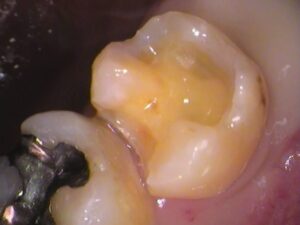

虫歯を全部とると、

このような状態です。

検知液で染まらないところまできました。

内部は健康な黄色い象牙質が見えています。

歯の神経までは達しませんでしたので、

神経の治療はしなくて済みました。